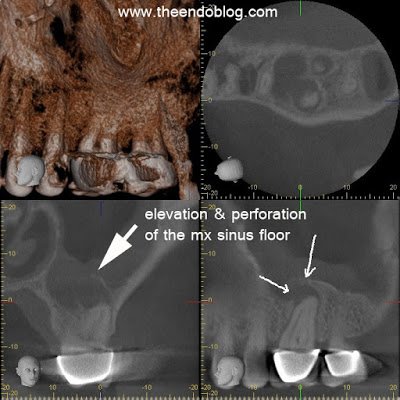

CBCT (J. Morita Veraviewepocs 3De) demonstrates a large periapical radiolucency around the mesio-buccal root. The sagittal and coronal views both show elevation in the floor of the sinus (halo effect) as well as perforation of the floor of the sinus. Endodontic treatment is required BEFORE sinus treatment. Failure to address the odontogenic source of the sinus infection will result in recurrent sinus infections.